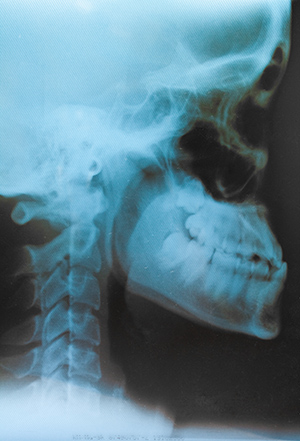

Esta prueba se hace en rayos X, dura entre 15 minutos y media hora y damos un bolo alimentario con un contraste para poder ver a través de rayos X hacia dónde va este bolo.

Este paciente lo prepara en boca mientras vamos viendo qué pasa a través de rayos X y después lo traga.

Podemos ver a través de esta prueba si va hacia la vía respiratoria, si va a la vía deglutoria, si hay algún problema entre medio o qué es lo que está pasando.